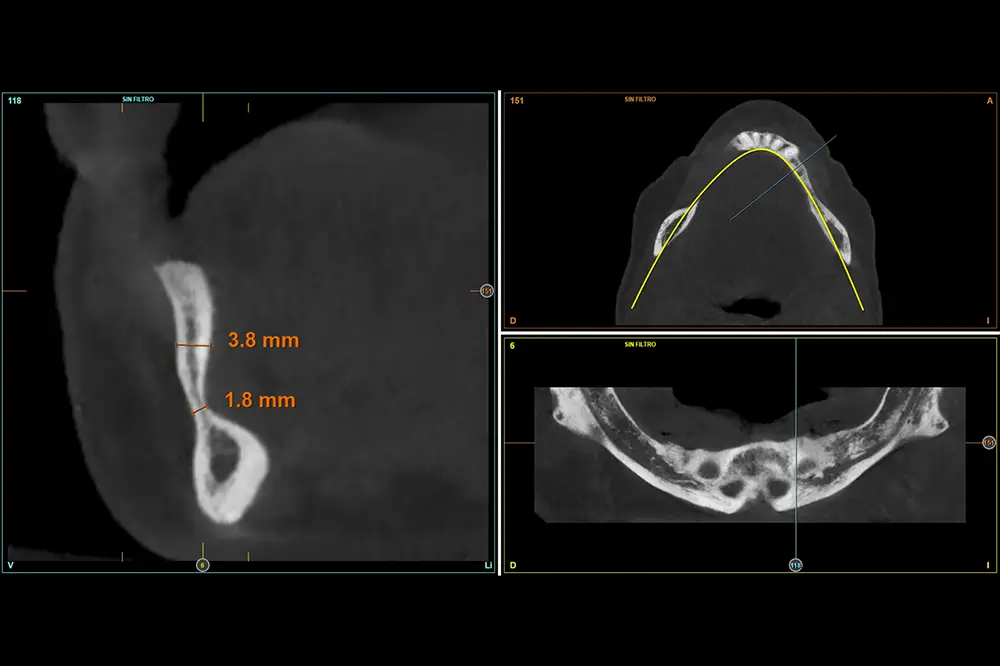

Figuras 8-11. Cortes seccionales del cone-beam de planificación del tercer cuadrante, donde podemos observar la extrema atrofia horizontal que encontramos en algunas localizaciones, con menos de 4 mm de anchura. Por ello, se planifican implantes de 2,5 mm en todo el cuadrante.